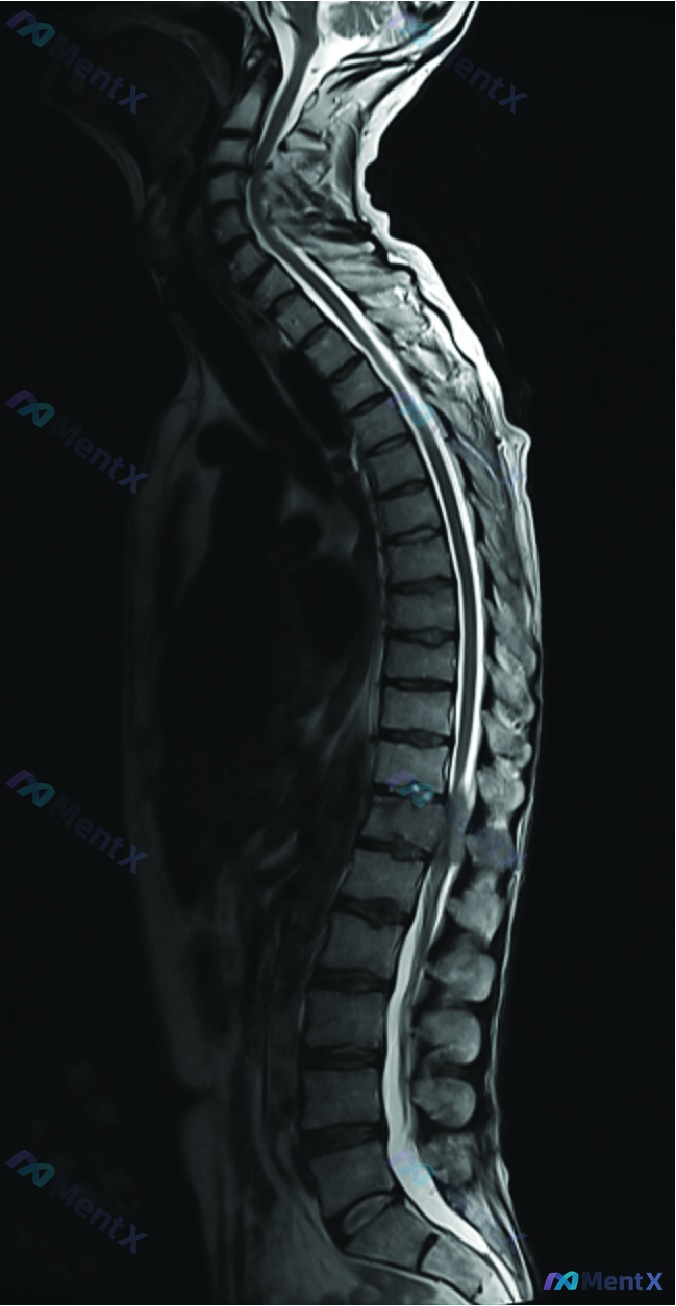

提供的是全脊柱MRI(T2加权矢状位),原始报告的描述是:

多节段脊柱退行性改变,包括颈椎序列平直、多节段椎间盘突出/膨出、骨质增生、韧带肥厚,伴多节段椎管狭窄;脊髓实质未见明显信号异常。